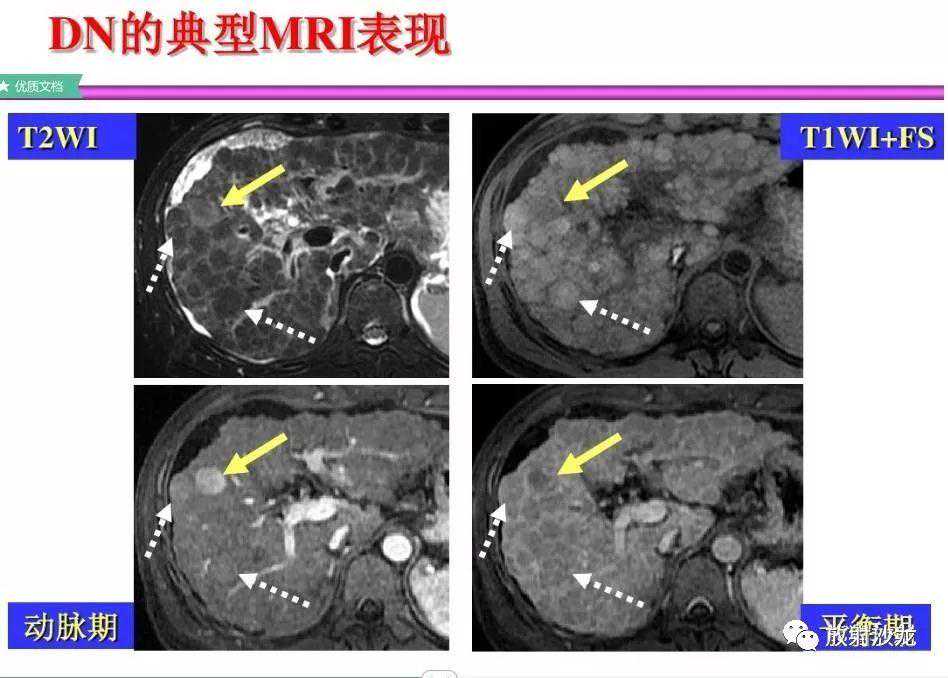

各基本序列信号特征

SSTSE:冠状T2WI,肝硬化,腹水,肝内多发低信号结节;

TSEfatsat:T2WI压脂,所有结节均呈低信号;

ART:动脉期,较大结节强化较明显,其余结节均不同程度有强化;

DEL:延迟期,大结节及其他结节均未见明显肿瘤包膜。

肝硬化,DN,MRI表现:

A~D:影像表现如上所述。

E:反相位,大部分肝结节呈较高信号;

F:同相位,肝内部分结节因铁沉积呈低信号;脾脏亦可见低信号的Gamna-Gandy小体;

G:动脉期,局部放大图像,大结节强化较明显;

H:延迟期,局部放大图像,大结节并未见肿瘤包膜。